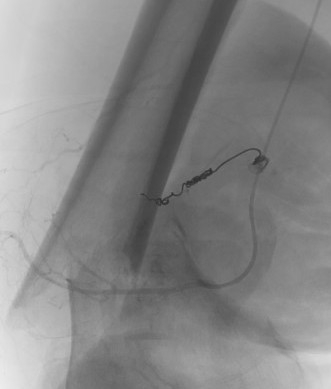

Pre-operative Arterial Embolization

Indications

- renal cell carcinoma

- thyroid carcinoma

Results

- embolisation of RCC metastasis in 107 patients

- success in 96%

- all patients had variable ischemic pain for 2 - 4 day

- 41 cases with embolization prior to surgery compared to 41 cases without

- embolization reduced blood loss, transfusion, and surgical times